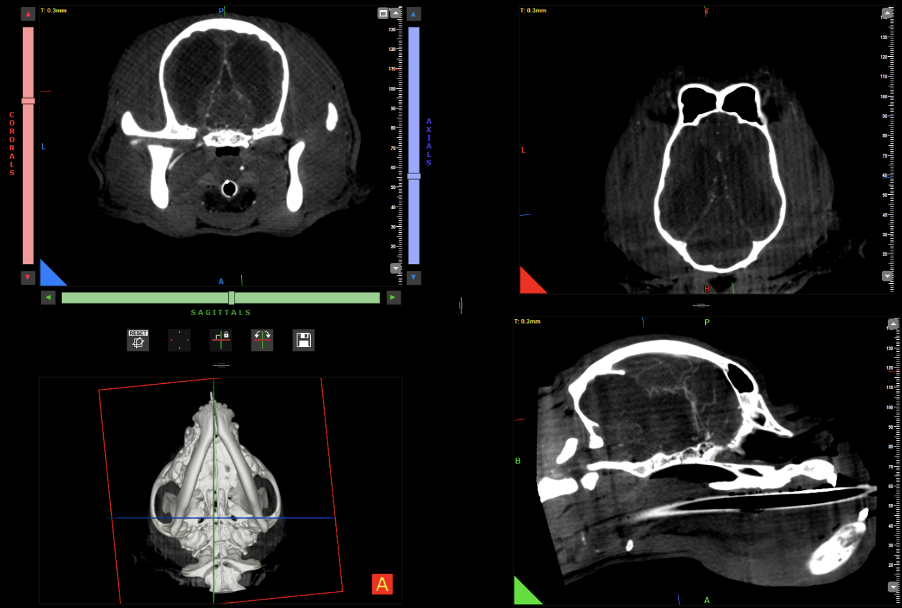

Kopf und Wirbelsäule: Auch in diesem Segment sind CBCT Einsätze aussagekräftig und erfolgreich – hier werden Scans zur genauen Diagnosestellung vom MRT abgelöst, wenn auch die zukünftige Optimierung mittels künstlicher Intelligenz die Bildqualität nochmals absehbar erhöhen wird (Abb. 7 & 8).